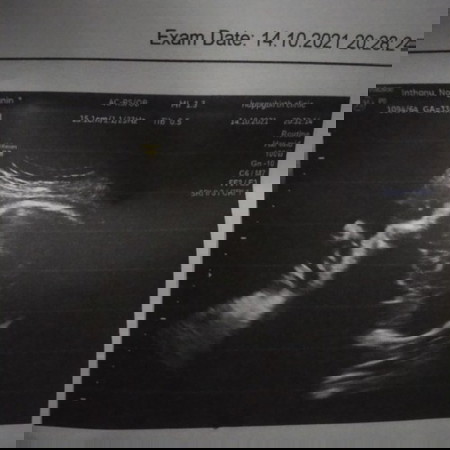

ลื่นล้มในห้องน้ำค่ะ เอาก้นลง ปวดก้นปวดหลังมาก ลูกกลับหัวแล้วด้วย ตัวเองเจ็บไม่เท่าไหร่ แต่เป็นห่วงลูกมาก เพิ่งไปอัลตร้าซาวมา ลูกแข็งแรงดีปกติดีทุกอย่าง แต่ดันมาลื่นล้มอีก เครียดเลยค่ะ ตอนนี้คอยสังเกตอาการตัวเองอยู่ 😭